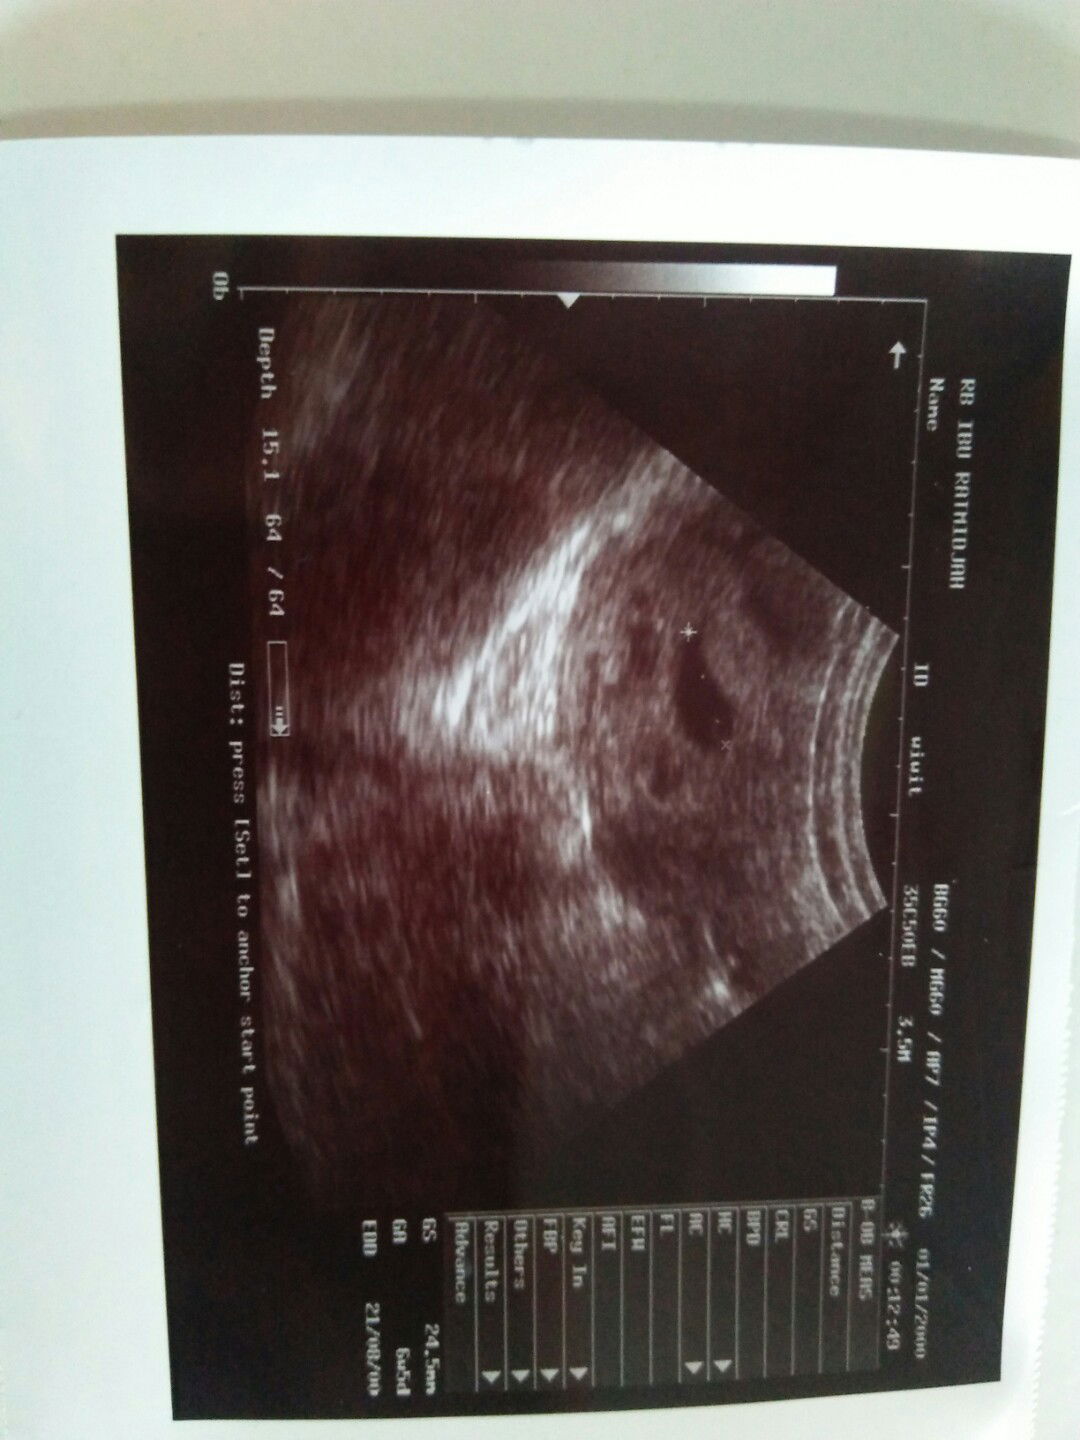

Bun mau tanya ...usia kandungan saya kalau saya hitung sudah menginjak 11 minggu ... kemarin saya usg kata nya baru ada kantung nya ajj. seharus nya bayi nya sudah ada Dan banyak darah menyelimuti kantung itu ...saya di sarankan untuk usg ulang 2 minggu kedepan ...dan saya juga sekarang mengalami pendarahan seperti mensturasi ..saya coba tespeck hasil nya masih positif .apa ini pertanda ke guguran atw gimana minta penjelasan nya buat yang sudah pengalaman bun ...ini hasil usg nya tadi malam